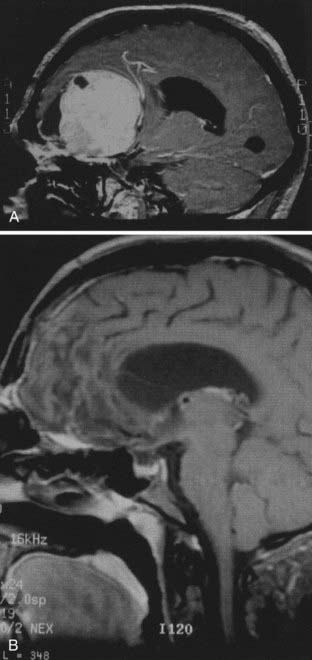

健康・医学 Meningiomas, Part II (Volume 170) i2 健康・医学 Meningiomas, Part II (Volume 170) i2 Meningiomasの詳細情報

健康・医学 Meningiomas, Part II (Volume 170) i2 Meningiomas。Regression of Intracranial Meningiomas Following Treatment。Unveiling a Biomarker Signature of Meningioma: The Need for。Meningiomas, Part II (Volume 170) (Handbook of Clinical Neurology, Volume 170) ハードカバー – 2020/8/14英語版 Michael W. McDermott MD (編集)※中古品のため、使用できれば良いという方のみのご購入をお待ちしております。筋骨格系のキネシオロジー。※商品状態の少々の見落としはご理解下さい。骨形態計測ハンドブック/高橋栄明 著。※都合により発送方法を変更する場合があります。【美品・書き込みなし】精神薬理学エセンシャルズ/精神科治療薬の考え方と使い方。。The Evolving Classification of Meningiomas: Integration of。角に少々イタミあり。中古品のため、多少のスレ、イタミ等ありますが、書き込みなく、とても良好な状態です。気管支鏡テキスト 第3版。【美品】カパンジー機能解剖学(全3巻)。※値引交渉にはお答え致しません。※希少品の為、定価より高額の場合があります。常用カイロプラクティックマニュアル。【裁断済】スキル美容外科手術アトラス 眼瞼。【佐川急便/日本郵便から佐川急便/日本郵便及びその逆等】※ビニールにて梱包し発送致しますが、保管、輸送によるイタミ等はご容赦下さい。※コメント不要、即購入にてご注文お願いします。早わかり犬と猫の臨床 小動物臨床ハンドブックシリーズ 5

16153-9/asset/2fac6123-c7b5-4672-9706-47561c05fa86/main.assets/gr2_lrg.jpg)